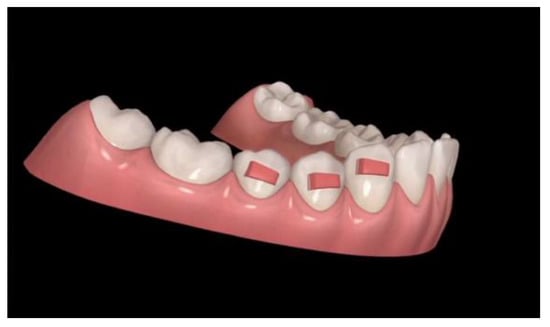

Figure 4. Conventional horizontal rectangular attachments.

Since aligners need retention to express vertical movements, such as extrusion or intrusion of posterior teeth, it is useful that the application of retention by conventional horizontal rectangular attachments are 4 mm large on premolars and, if possible, 5 mm on canines (Figure 4). If extrusion of the premolars is desired, the attachment design is modified from horizontal rectangular to gingival beveled (Figure 5). The attachments of this shape and dimension are necessary to improve the surface of force application to premolars and canines and to prevent dislodgement of aligners during an anterior intrusion.